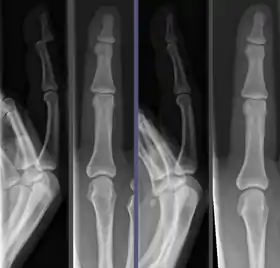

![]() Joint dislocation in the DIP of the third finger before (left images) and after (right images) reduction. | |

Because the process of reduction can briefly be intensely painful, it is commonly done under a short-acting anesthetic, sedative, or nerve block. Once the fragments are reduced, the reduction is maintained by application of casts, traction, or held by plates, screws, or other implants, which may in turn be external or internal. It is very important to verify the accuracy of reduction by clinical tests and X-ray, especially in the case of joint dislocations.